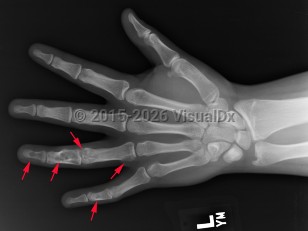

Ollier disease and Maffucci syndrome are nonhereditary conditions that present as multiple enchondromas. Ollier disease involves multiple asymmetric enchondromas of the digits. It is most commonly seen in childhood. These slow-growing tumors usually stop growing after puberty, but masses can create deformity and limb asymmetry. Pathologic fractures may be seen. Ollier disease has a 15%-20% risk for secondary chondrosarcoma.

Classic history and presentation: The proximal phalanx is the typical location. These tumors are also common incidental findings in the distal femur, proximal humerus, and tibia. Mean length is usually less than 5 cm.

Prevalence: Enchondroma is a latent lesion that comprises 15%-25% of cartilage tumors. It is the most common hand tumor, accounting for 90% of cases. Enchondroma usually presents in the third and fourth decades of life and occurs equally between both sexes.

Pathophysiology: Enchondroma pathophysiology is believed to involve incomplete endochondral ossification in which physeal remnants become entrapped in the medullary cavity of the metaphysis and proliferate. In the hand, enchondromas are typically diagnosed after a pathologic fracture. Elsewhere, they are typically an asymptomatic incidental finding on x-ray or advanced imaging performed for other reasons. Pain is usually due to a nearby abnormality rather than the tumor itself.